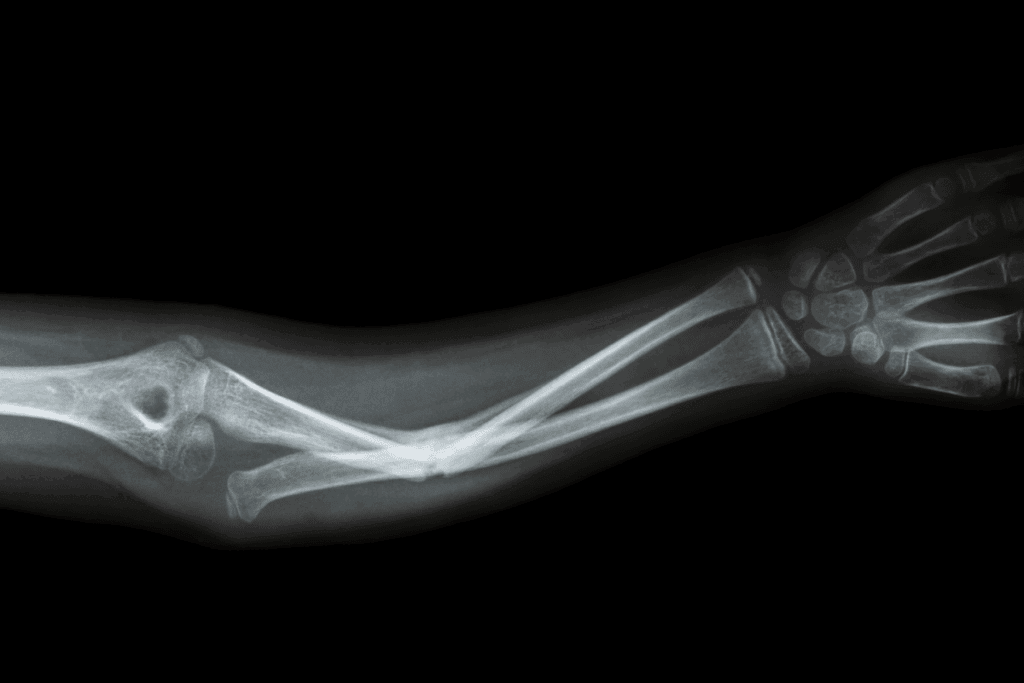

Upper Extremity Fracture Complications

Fractures in the arms, wrists, and hands can cause specific issues. These might include:

- Reduced mobility and strength in the affected arm or hand

- Nerve damage leading to numbness or tingling

- Impaired function of the wrist or elbow

Common complications of upper extremity fractures include malunion, where the bone heals in an incorrect position, and nonunion, where the bone fails to heal properly.